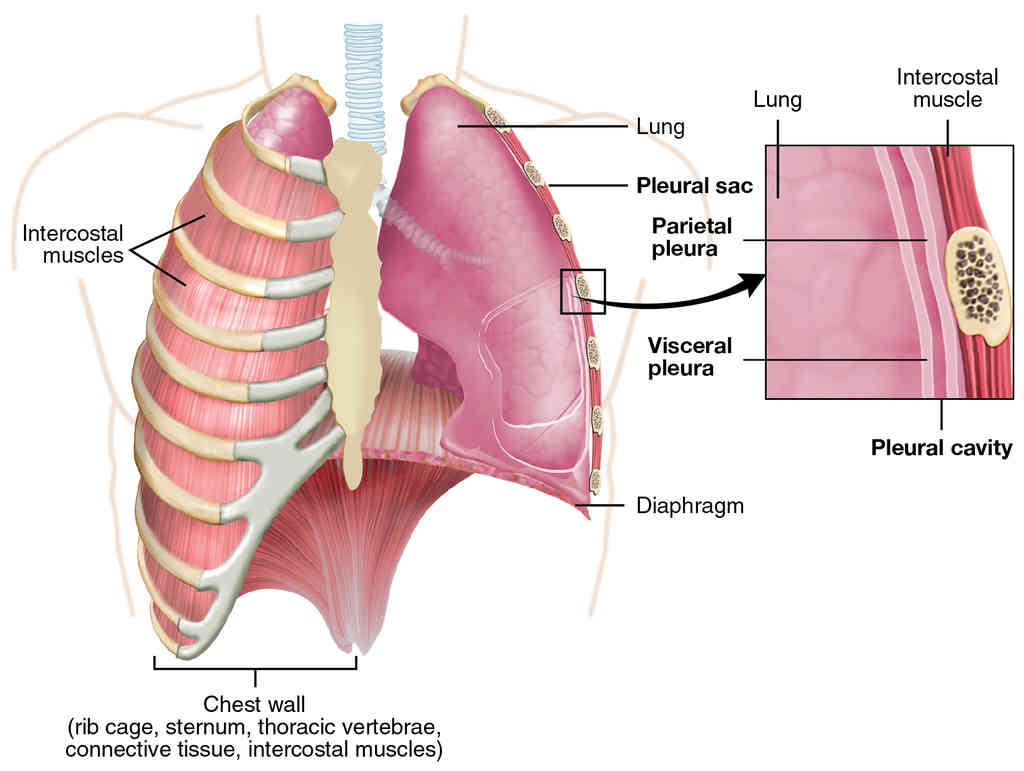

Anatomy, Physiology and Histology

This page is under construction. For now, it is just a resource of the images found in the OpenStax Anatomy and Physiology Handbook. It wil slowly change into a revision tool. Each slide has a number. Use this to refer to the slide. When completed, it will have an unlabelled section, with labelled slides in parallel. On the unlabelled slides, write your answer and use the labelled slide to assess yourself. Keep track by also noting the number on each slide. Improvement at each attempt is important, more so than full marks on a first attempt.